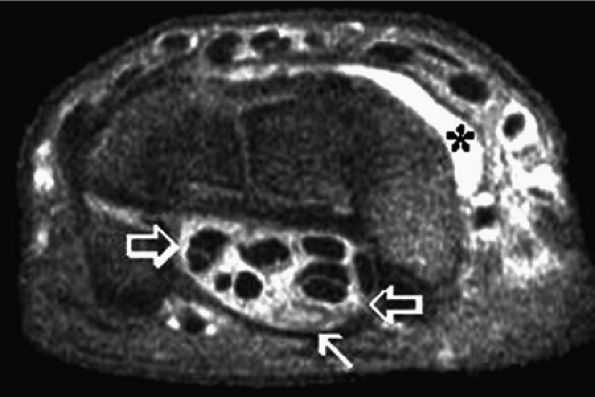

Chronic cubital tunnel syndrome may be caused by masses such as tumors, distended bursae, ganglions, hematoma, inflammatory pannus, gouty tophi, loose bodies, osteophytes, and scarring (Figs. 12.19 and 12.20)

FIGURE 12.19 ● Ulnar neuropathy secondary to compression by hemangioma. An axial post-gadolinium fat-suppressed T1-weighted image shows an avidly enhancing soft-tissue mass encasing (arrowhead) the ulnar nerve (solid arrow) in the medial aspect of the distal arm, consistent with a hemangioma (asterisk). Note invasion of the medial humerus by the mass (open arrow).

|